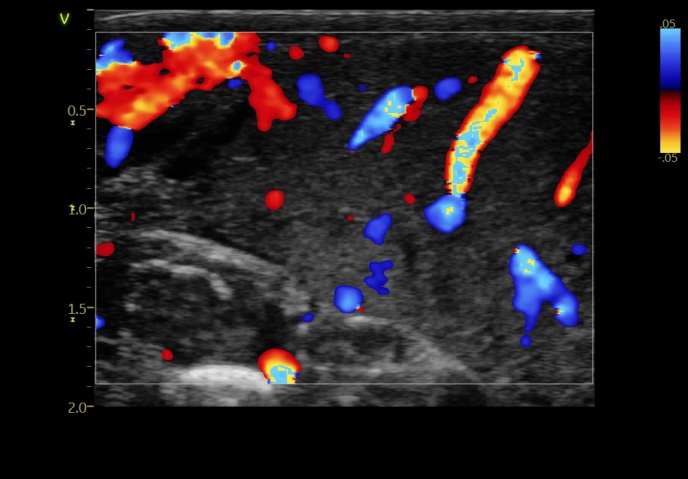

孕期B超发现胎儿右侧小腿皮下6.1*3.5cm略低回声实性团块,生后发现患儿右侧小腿巨大包块,大小约9*7.5*2.5cm。完善B超提示:右小腿前外侧皮下可见范围6.3*3.7*5.8cm低回声实性团块,考虑血管瘤可能,为求进一步治疗,由外院转入我院新生儿科。患儿入院后立即完善相关检查。为进一步明确诊断是否血管内皮瘤,王惠萍主任医师团队遂联系B超室何鑫教授行超声引导下穿刺活检。因CDFI提示:其内血流信号丰富,基底部可见较粗血管,穿刺风险极大。因此精准选择穿刺部位对减轻相关风险的意义尤为重要,团队为患儿在穿刺可能遇到的风险进行讨论并制定对应预案。经家属同意后,由超声介入科何鑫教授行超声引导下穿刺活检,穿刺整个过程很顺利,无明显出血,术后平安返回新生儿病房。患儿现生命体征平稳,等病理结果出来便可明确诊断,跟进下一步治疗。